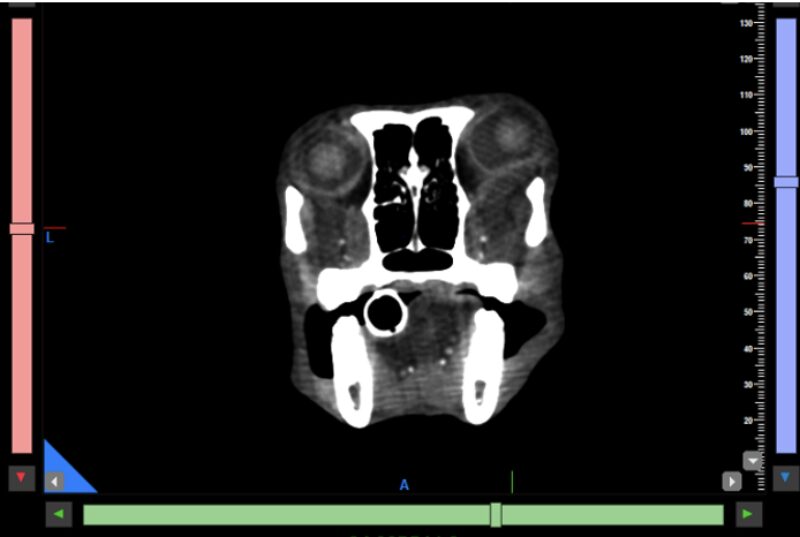

Kopf und Hals: Tumoren im und am Kopf lassen sich mit dem CBCT sehr präzise darstellen. Neben der exzellenten Beurteilung knöcherner Invasionen können auch Weichteilanteile zuverlässig abgegrenzt werden, was insbesondere für die präoperative Planung relevant ist. Kiefer- und Zahntumoren sowie komplexe dentale Erkrankungen profitieren weiterhin von der hohen Ortsauflösung des CBCT, die in diesen Bereichen einem klassischen Slice-CT überlegen sein kann. Bei brachycephalen Patienten hat sich das präoperative Dental-CT als Standard etabliert und ersetzt häufig eine Vielzahl konventioneller Dentalröntgenaufnahmen (Abb. 1 & 2).